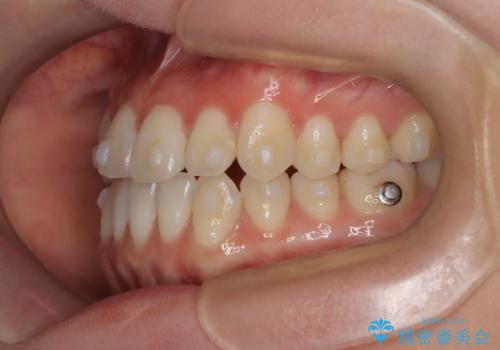

- 八重歯と、右上前歯(2番)が下の歯より内側に入っている反対咬合を気にされてご来院されました。精密な検査の結果、八重歯と反対咬合を同時に改善するためには、歯列全体にスペースを確保する必要があると判明。患者様のご希望から、透明で目立たないインビザライン(マウスピース矯正)による治療計画を立案しました。奥歯全体を奥へ動かす遠心移動でスペースを作り、これらの複雑な問題を一括で解消することを目指します。

今回の矯正治療では、透明なマウスピース型の装置インビザラインを使用しました。治療は、緻密なデジタル計画に基づき、奥歯から順に歯列全体を後方へ移動させる遠心移動を実施。これにより、八重歯を正しい位置に並べるためのスペースを確保しました。同時に、右上の2番を前方に誘導することで反対咬合を解消。結果として、抜歯することなく八重歯と反対咬合という複数の問題が改善され、機能的で美しい歯並びを獲得していただけました。